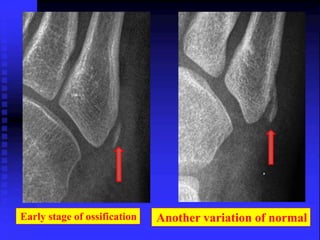

Physeal Fracture

Early stage of ossification Another variation of normal

Normal

Fracture

Early stage ofossification Another variation of normal